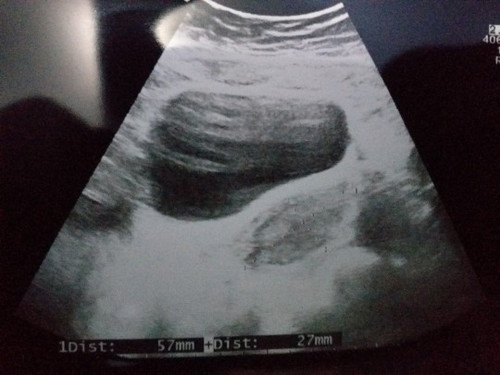

Usg 4w hasilnya begini

Ada engga disini bunda" yg usg uk 4w masih kosong karna kemungkinan masih kecil kata dokternya. 2minggu lagi suruh periksa lagi klo masih gk keliatan mau di usg transvaginal. Share dong bunda gambar hasil usg yg 4w bunda" disini?